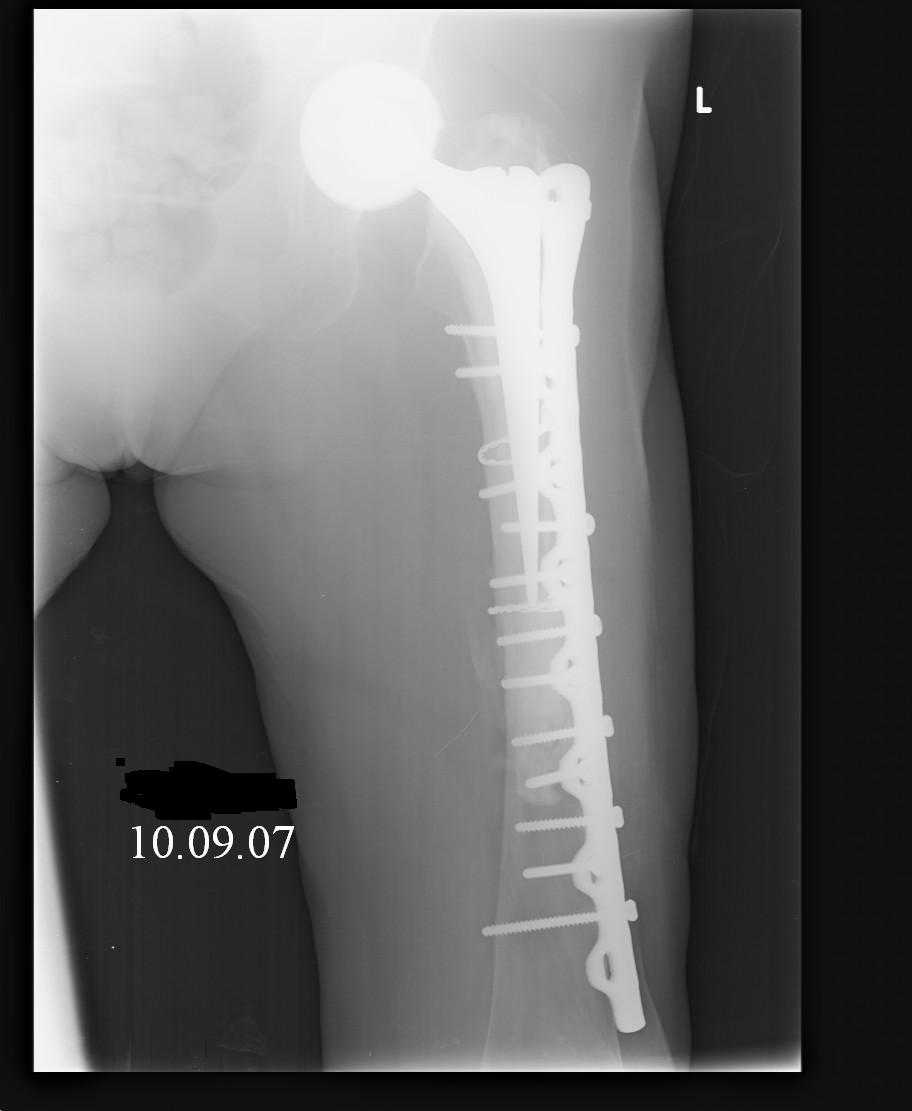

Reminded me of a case I did a couple years ago - 30 year old woman with juvenile rheumatoid arthritis and a nonunion below her stem. Fixed with retrograde nail which docked with the stem and a lateral locking plate. Image attached. One of the companies should come up with a stem design and nail system that anticipates this need.

Jeff Anglen, M.D.